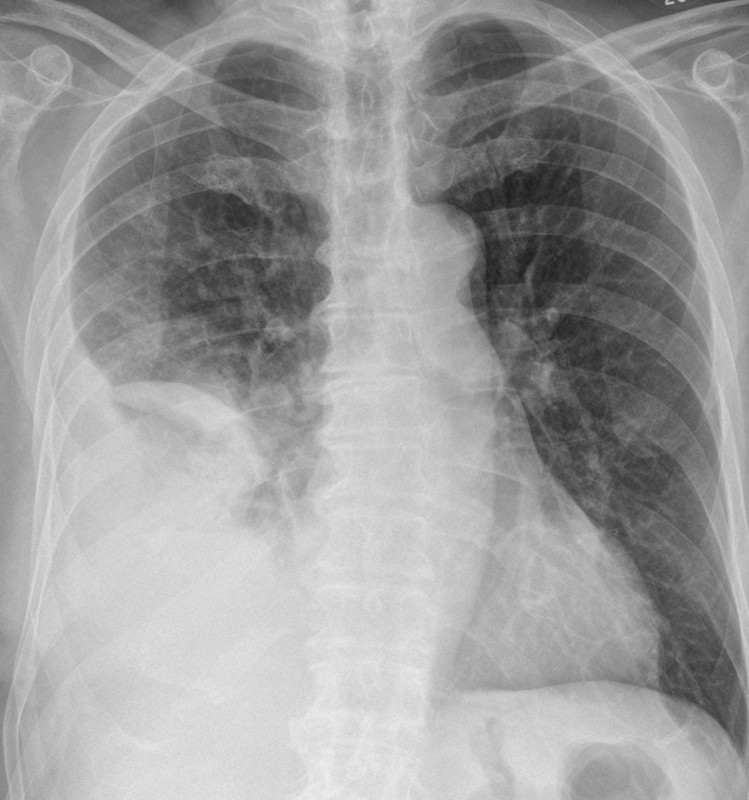

- CXR may show consolidation and an effusion

- All patients with a pleural effusion in association with

sepsis or a pneumonic illness require diagnostic pleural

fluid sampling